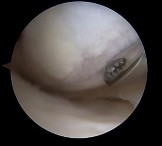

Which image seen during arthroscopic treatment is most likely associated with this patient’s condition?

An otherwise healthy 31-year-old man has had right knee pain for the past 9 months. His former physician

administered a cortisone injection and ordered 6 months of physical therapy. The patient later had an arthroscopy with debridement of the right knee by another physician and completed another course of physical therapy. The patient received minimal relief from these treatments and still is not able to walk longer distances or go on hikes. On examination, he is a healthy appearing male with a body mass index of 24 kg/m2. He has a small effusion, minimal quadriceps atrophy, no tenderness about the knee, full range of motion, stable to varus and valgus stress at 30° of flexion, a grade 1 Lachman test, and a normal posterior drawer. Figures 1 through 4 are his arthroscopic views, radiograph and MRI scan from his prior surgical procedure. What is the next most appropriate step in treatment?